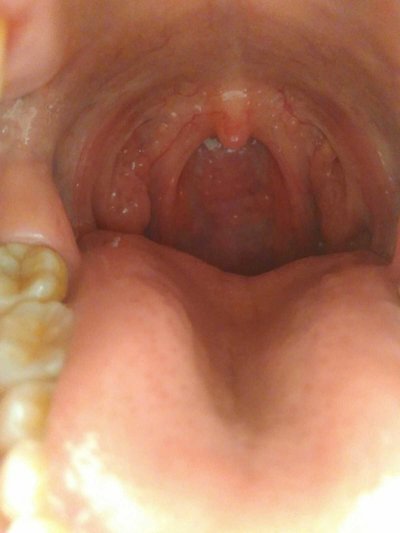

Cold cough is a kind of airway allergic inflammation, is a very common symptom, almost everyone has experienced the trouble of cough, especially in the cold winter season, many elderly people, children and patients even dare not go out, greatly affecting the quality of life. Cold cough symptom? Let's talk about it

Cough may be the only symptom of asthma, mainly long-term stubborn dry cough, often induced by inhalation of pungent odor, cold air, contact with allergens, exercise or upper respiratory tract infection, some patients do not have any incentives.